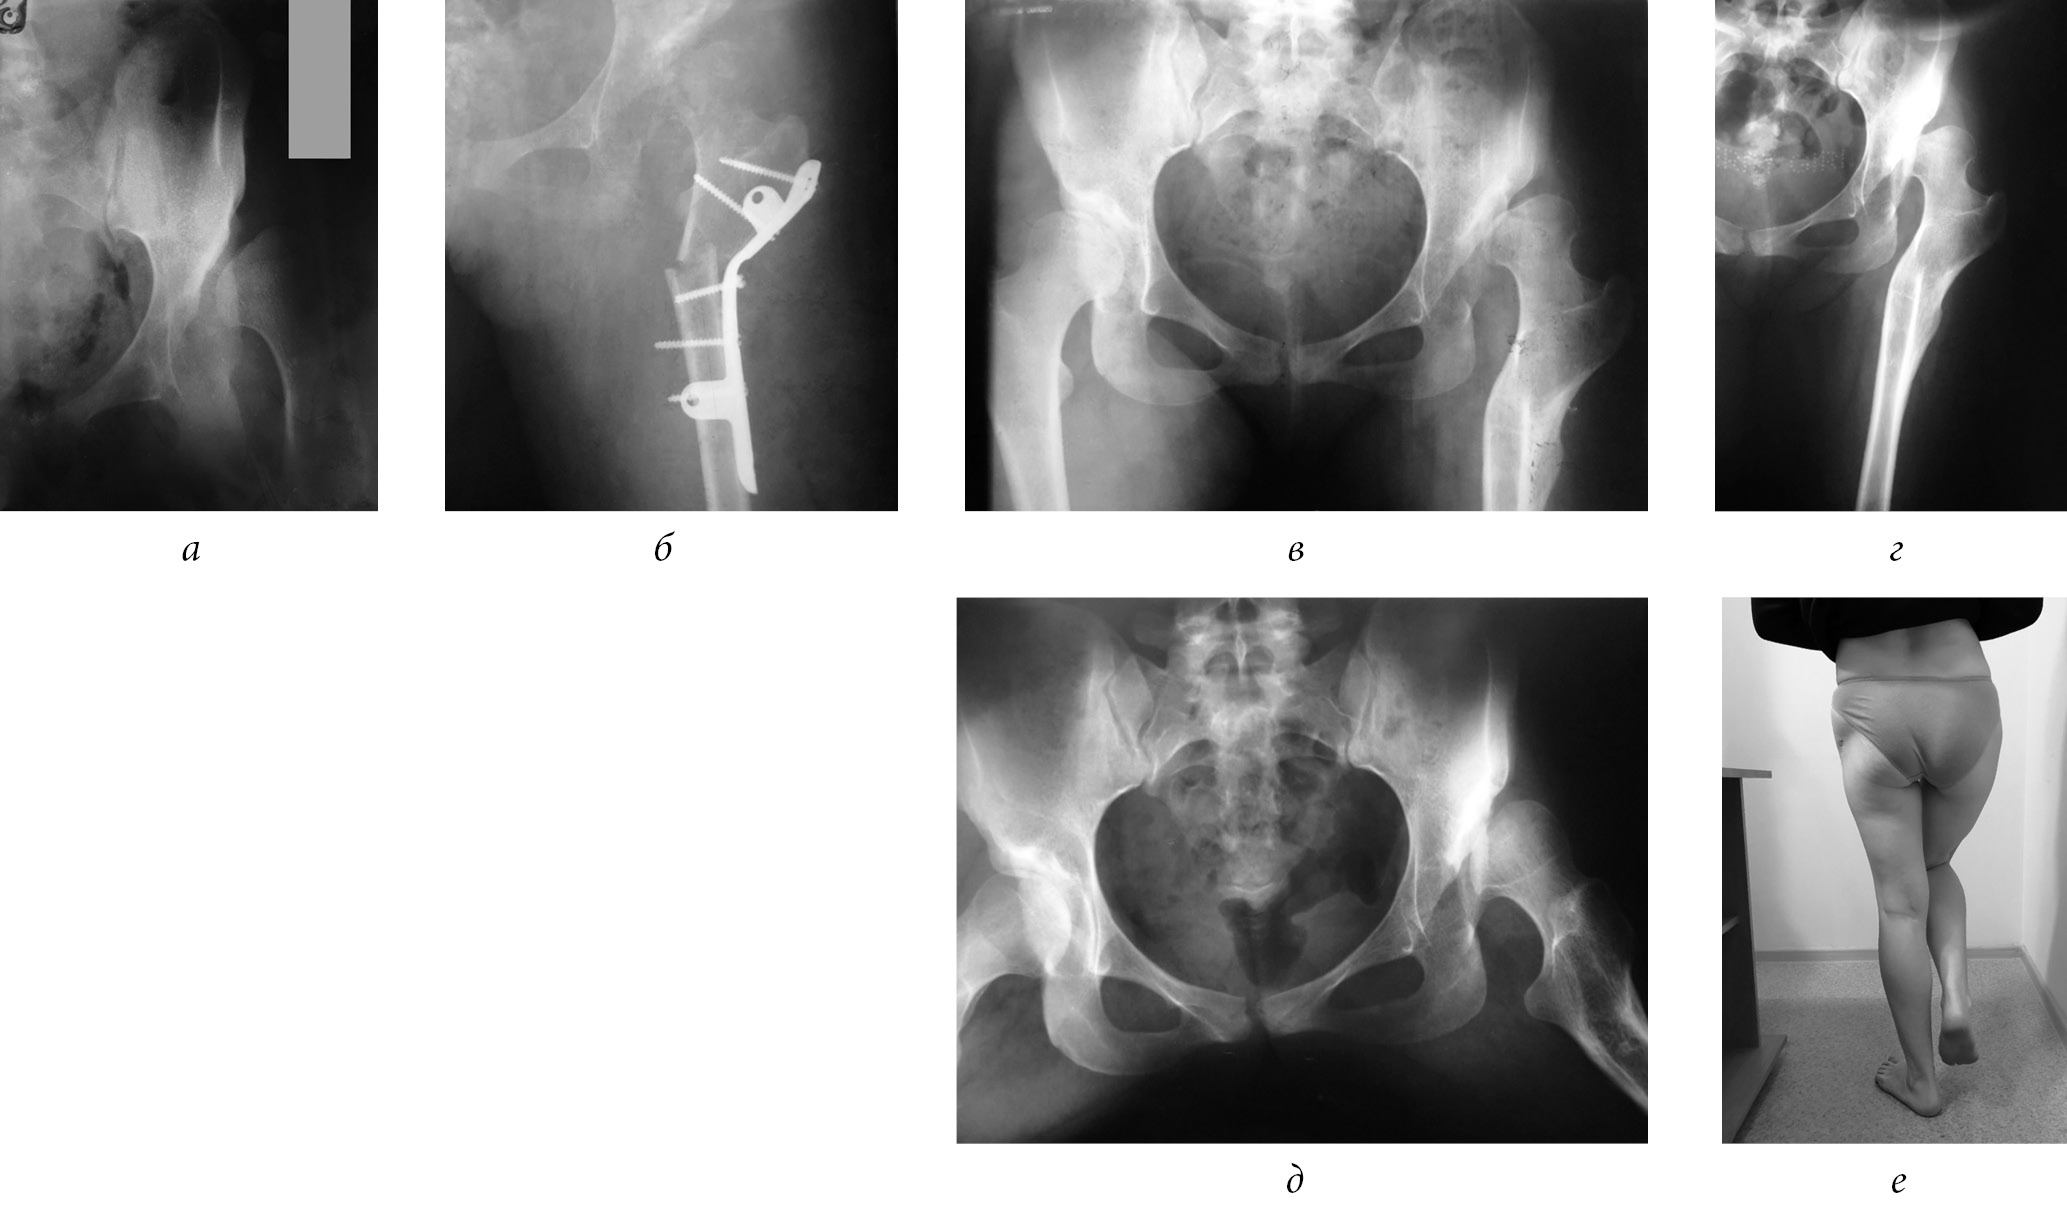

At the age of 15 years, the patient was admitted with complaints of pain in the hip joint on the left, lameness, shortening of the limb by 4 cm. The radiograph revealed a dislocation of the left hip with moderate neoarthrosis in the peri-acetabular region, subchondral sclerosis (Fig. 5, a). After the examination, taking into account the X-ray image, the patient’s age and clinical data, in 2004 a surgical intervention was performed according to the technique we proposed (Fig. 5, b). The postoperative period was uneventful. The wound healed by primary intention. After a week, rehabilitation treatment was started, the patient was trained in rehabilitation treatment and was discharged home after 14 days with the use of a “derotational boot” for 2 months.

Fig. 5. Radiographs of patient D. with congenital dislocation of the hip on the left: а — before surgery (2004); b — after the surgery (2004); c — one year after removal of the surgical hardware; d, e — 15 years after the surgery (2018); f — Trendelenburg symptom 15 years after the surgery

A year later, the hardware was removed (Fig. 5, c) and rehabilitation treatment continued. A follow-up examination was performed 15 years after surgery (2018); there were no complaints — the patient walked with a full load on the limb, without additional support, with a slight limp on the left lower limb. Functional shortening of the left lower limb by 1.5 cm is noted. The radiograph of the left lower limb reveals a restored biomechanical axis of the limb. The proximal end of the hip is valgized, the collum-diaphyseal angle is 145°, and the support points for the pelvis have been formed in the region of the lower edge of the acetabulum and a small trochanter (Fig. 5, d, e). The patient is married, has two children, is employed, and she is satisfied with the result of the surgery. The Trendelenburg symptom is not prominent (Fig. 5, f). Periodically, in the summer, she undergoes independent rehabilitation treatment in the territory of the North Caucasus. With a prolonged load on the limb, a minor pain syndrome is noted, which decreases with intake of non-steroidal anti-inflammatory drugs. The patient is not yet ready for hip joint replacement.